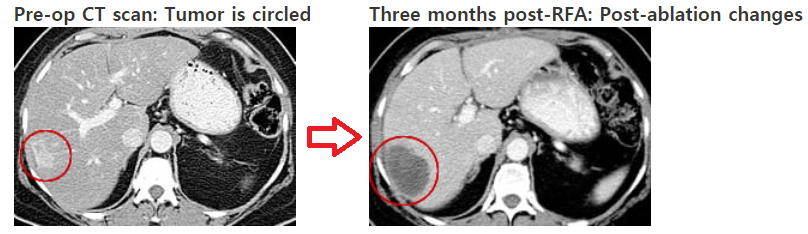

간암의 치료 3. RFA (고주파열치료)

mass size 3cm 이내, 3개 이하인 경우 / mass size 2cm 이하인 경우 효과가 높음

RFA 란 radio frequent ablation 으로

1) CT guide RFA : CT로 mass 위치를 확인하면서 고주파열로 liver mass를 태우는 것

2) Sono guide RFA : sono 로 mass 위치를 확인하면서 고주파열로 liver mass를 태우는 것

시술 후 CT를 찍어 ablation 여부를 확인하고 total ablation 이 되면 시술 종료